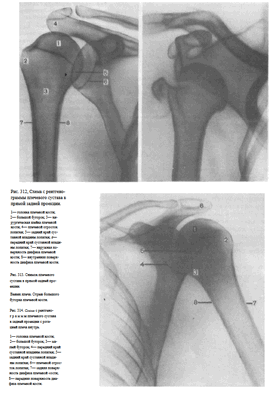

Укладка больного при выполнении снимков. Предложено несколько вариантов укладки: f. Больной лежит на спине. Снимаемая конечность вытянута вдоль туловища, находится в положении супинации (при этом большой бугорок плечевой кости занимает краеобразующее положение).

Кассета размером 18X24 см расположена на столе в продольном положении. Верхний край ее на 3 см выше надплечья.

Центральный пучок рентгеновского излучения направляют отвесно на проекцию суставной щели —на 3—4 см дистальнее плечевого отростка лопатки, легко прощупываемого под кожей (рис. 308).

2. С целью устранения проекционного наслоения плечевого отростка лопатки на головку плечевой кости и для более плотного прилежания головки к кассете предложено верхний край кассеты приподнимать так, чтобы кассета образовывала с плоскостью стола угол в 20—25° (рис. 309).

3. Для детального изучения рентгеновской суставной щели плечевого сустава на всем ее протяжении с целью исключения наслоения изображения головки плечевой кости и суставной поверхности лопатки предложено при укладке больного поворачивать его на 30—45° в исследуемую сторону. При этом задняя поверхность лопатки устанавливается параллельно плоскости кассеты (что контролируется подводимой под нее ладонью), а суставная поверхность лопатки оказывается расположенной перпендикулярно к кассете. Плоскость, соединяющая мыщелки плечевой кости, параллельна плоскости стола (рис. 310).

4. Иногда применяют укладку для рентгенографии плечевого сустава в задней проекции с ротацией плеча внутрь. Положение больного, расположение кассеты, центрация пучка рентгеновского излучения остаются те же; разница лишь в том, что кисть снимаемой руки находится в положении пронации — ладонью к столу (рис.311) — либо рука согнута в локтевом суставе, и кисть лежит на животе больного.

На снимках плечевого сустава хорошо видны головка плечевой кости, суставная впадина лопатки, плечевой отросток лопатки.

На рентгенограмме, произведенной в условиях супинации кисти, хорошо виден большой бугорок плечевой кости, который здесь является краеобразующим (рис.312, 313). На снимках, произведенных в условиях пронации кисти, большой бугорок виден хуже, но по медиальному контуру над хирургической шейкой становится виден малый бугорок (рис.314). Медиальный и латеральный контуры тела плечевой кости при этих двух вариантах укладки на снимках образованы разными ее поверхностями. На снимке при супинации кисти медиальный контур образован внутренней, а латеральный — наружной поверхностью тела плечевой кости; на снимке при пронации кисти медиальный контур отображает переднюю, а латеральный — заднюю поверхность тела плечевой кости.

Наиболее информативными для оценки плечевого сустава являются снимки, выполненные в условиях разгибания верхней конечности и супинации кисти. Снимки в задней проекции с ротацией плеча внутрь являются дополнительными или же выполняются в тех случаях, когда снимок в прямой задней проекции с разгибанием руки произвести не удается.